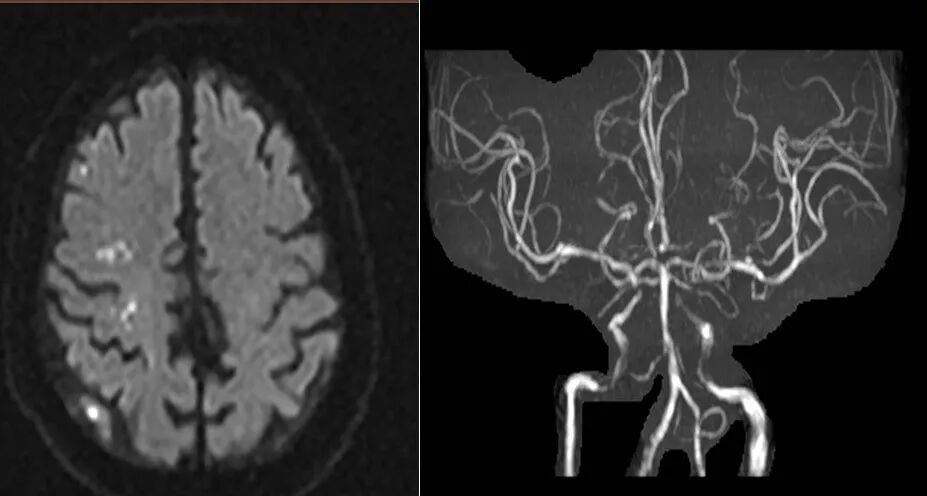

2022-07-21 颅脑MR。

DWI

MRA

重要影像结论:左侧额顶枕叶梗死灶。

DSA

重要影像结论:左侧颈内动脉C4段重度狭窄。